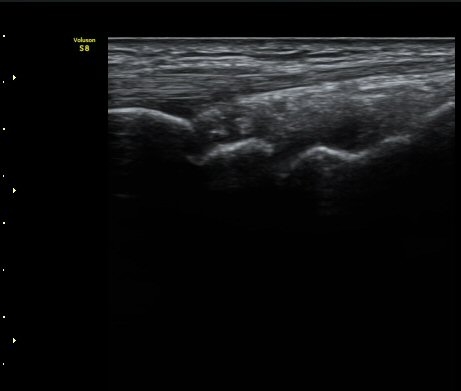

ÃÊÀ½ÆÄ °Ë»ç

ÁÖ»ó°ñ ¼±»ó°ñÀýÀº ´Ü¼ø¹æ»ç¼± ÃÔ¿µ ½Ã È®ÀεÇÁö ¾ÊÀº °æ¿ì°¡ ¸¹Àºµ¥ ÀÌ ¶§ ÃÊÀ½ÆÄ

°Ë»ç°¡ ÁÖ»ó°ñ °ñÀý Áø´Ü¿¡ ¸Å¿ì À¯¿ëÇÏ´Ù. ±×·¯¹Ç·Î ¼Õ¸ñ ´ÙÄ£ ÈÄ Áö¼ÓÀûÀÎ ÅëÁõÀ»

È£¼ÒÇϰí ÁÖ»ó°ñ ºÎÀ§ ¾ÐÅëÀ» º¸ÀÌ´Â °æ¿ì ÃÊÀ½ÆÄ°Ë»ç¸¦ ½ÃÇàÇÏ¿© ÁÖ»ó°ñ °ñÀý ¿©ºÎ¸¦

È®ÀÎÇØ¾ß ÇÑ´Ù.

ÃÊÀ½ÆÄ°Ë»ç¸¦ ½ÃÇàÇÒ ¼ö ¾ø´Â °æ¿ì´Â ÄÄÇ»ÅÍ ÃÔ¿µ°Ë»ç¸¦ ÁÖ»ó°ñ °ñÀýÀ» È®ÁøÇÒ ¼ö ÀÖ´Ù.